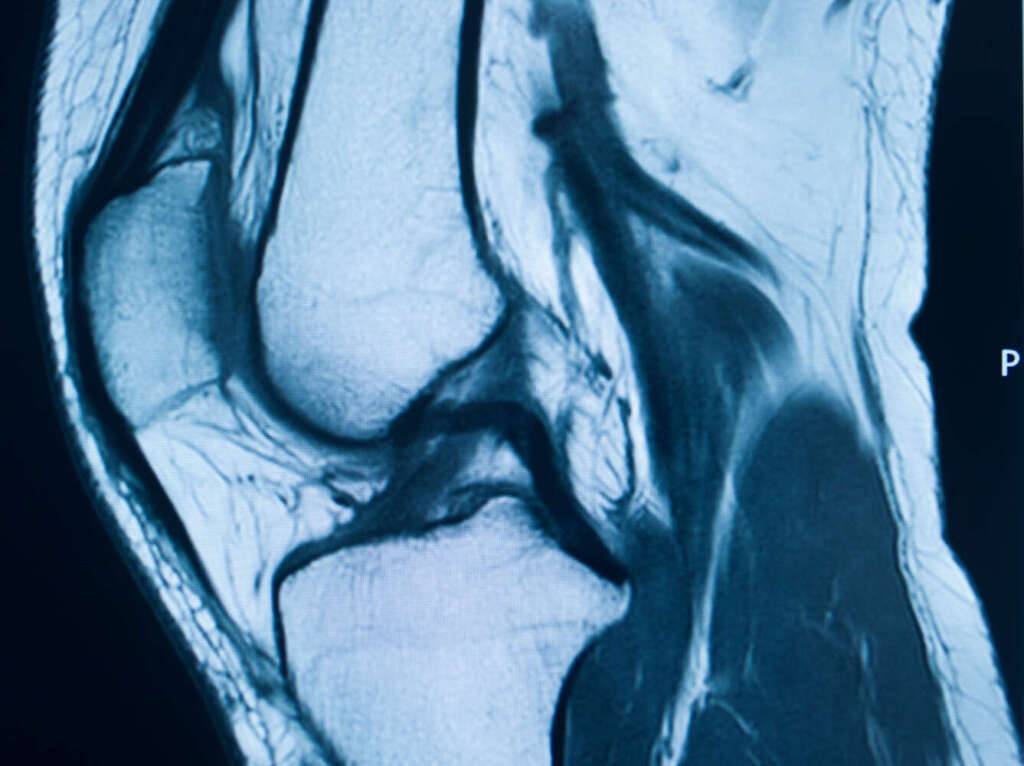

Das MRT ist im Grunde ein super-detailliertes Fotoalbum deines Knies. Es erstellt Schicht für Schicht Bilder von Knochen, Knorpeln, Bändern und Sehnen. Das Ganze funktioniert mit Magnetfeldern und Radiowellen – klingt futuristisch, ist aber eigentlich ganz simpel. Stell dir vor, es ist wie ein extrem hochauflösendes Selfie deines Knies von innen.

Aber warum überhaupt ein MRT? Nun, ein normales Röntgenbild zeigt nur die Knochen. Ein MRT kann viel mehr: Risse im Meniskus, Entzündungen, Knorpelschäden – all das, was mit bloßem Auge (oder einem herkömmlichen Röntgenbild) verborgen bleibt.